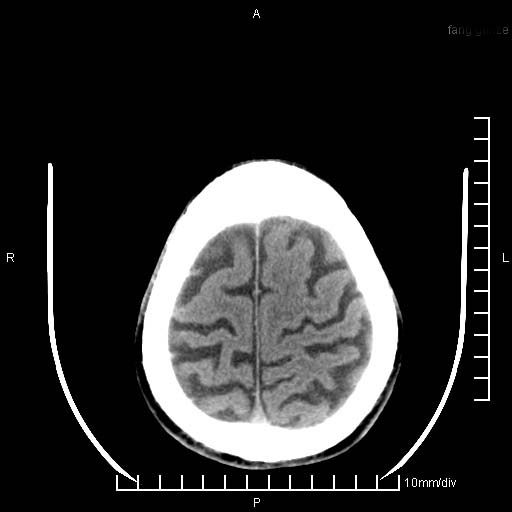

临床以双下肢浮肿,疼痛收治,无明显神经系统症状,既往无梗塞,出血病史。左颞叶见低密度灶,考虑什么?

考虑左侧颞叶脑软化灶。

无强化 无占位 软化灶吧

无强化、 无占位、局部脑沟增宽, 软化灶吧。